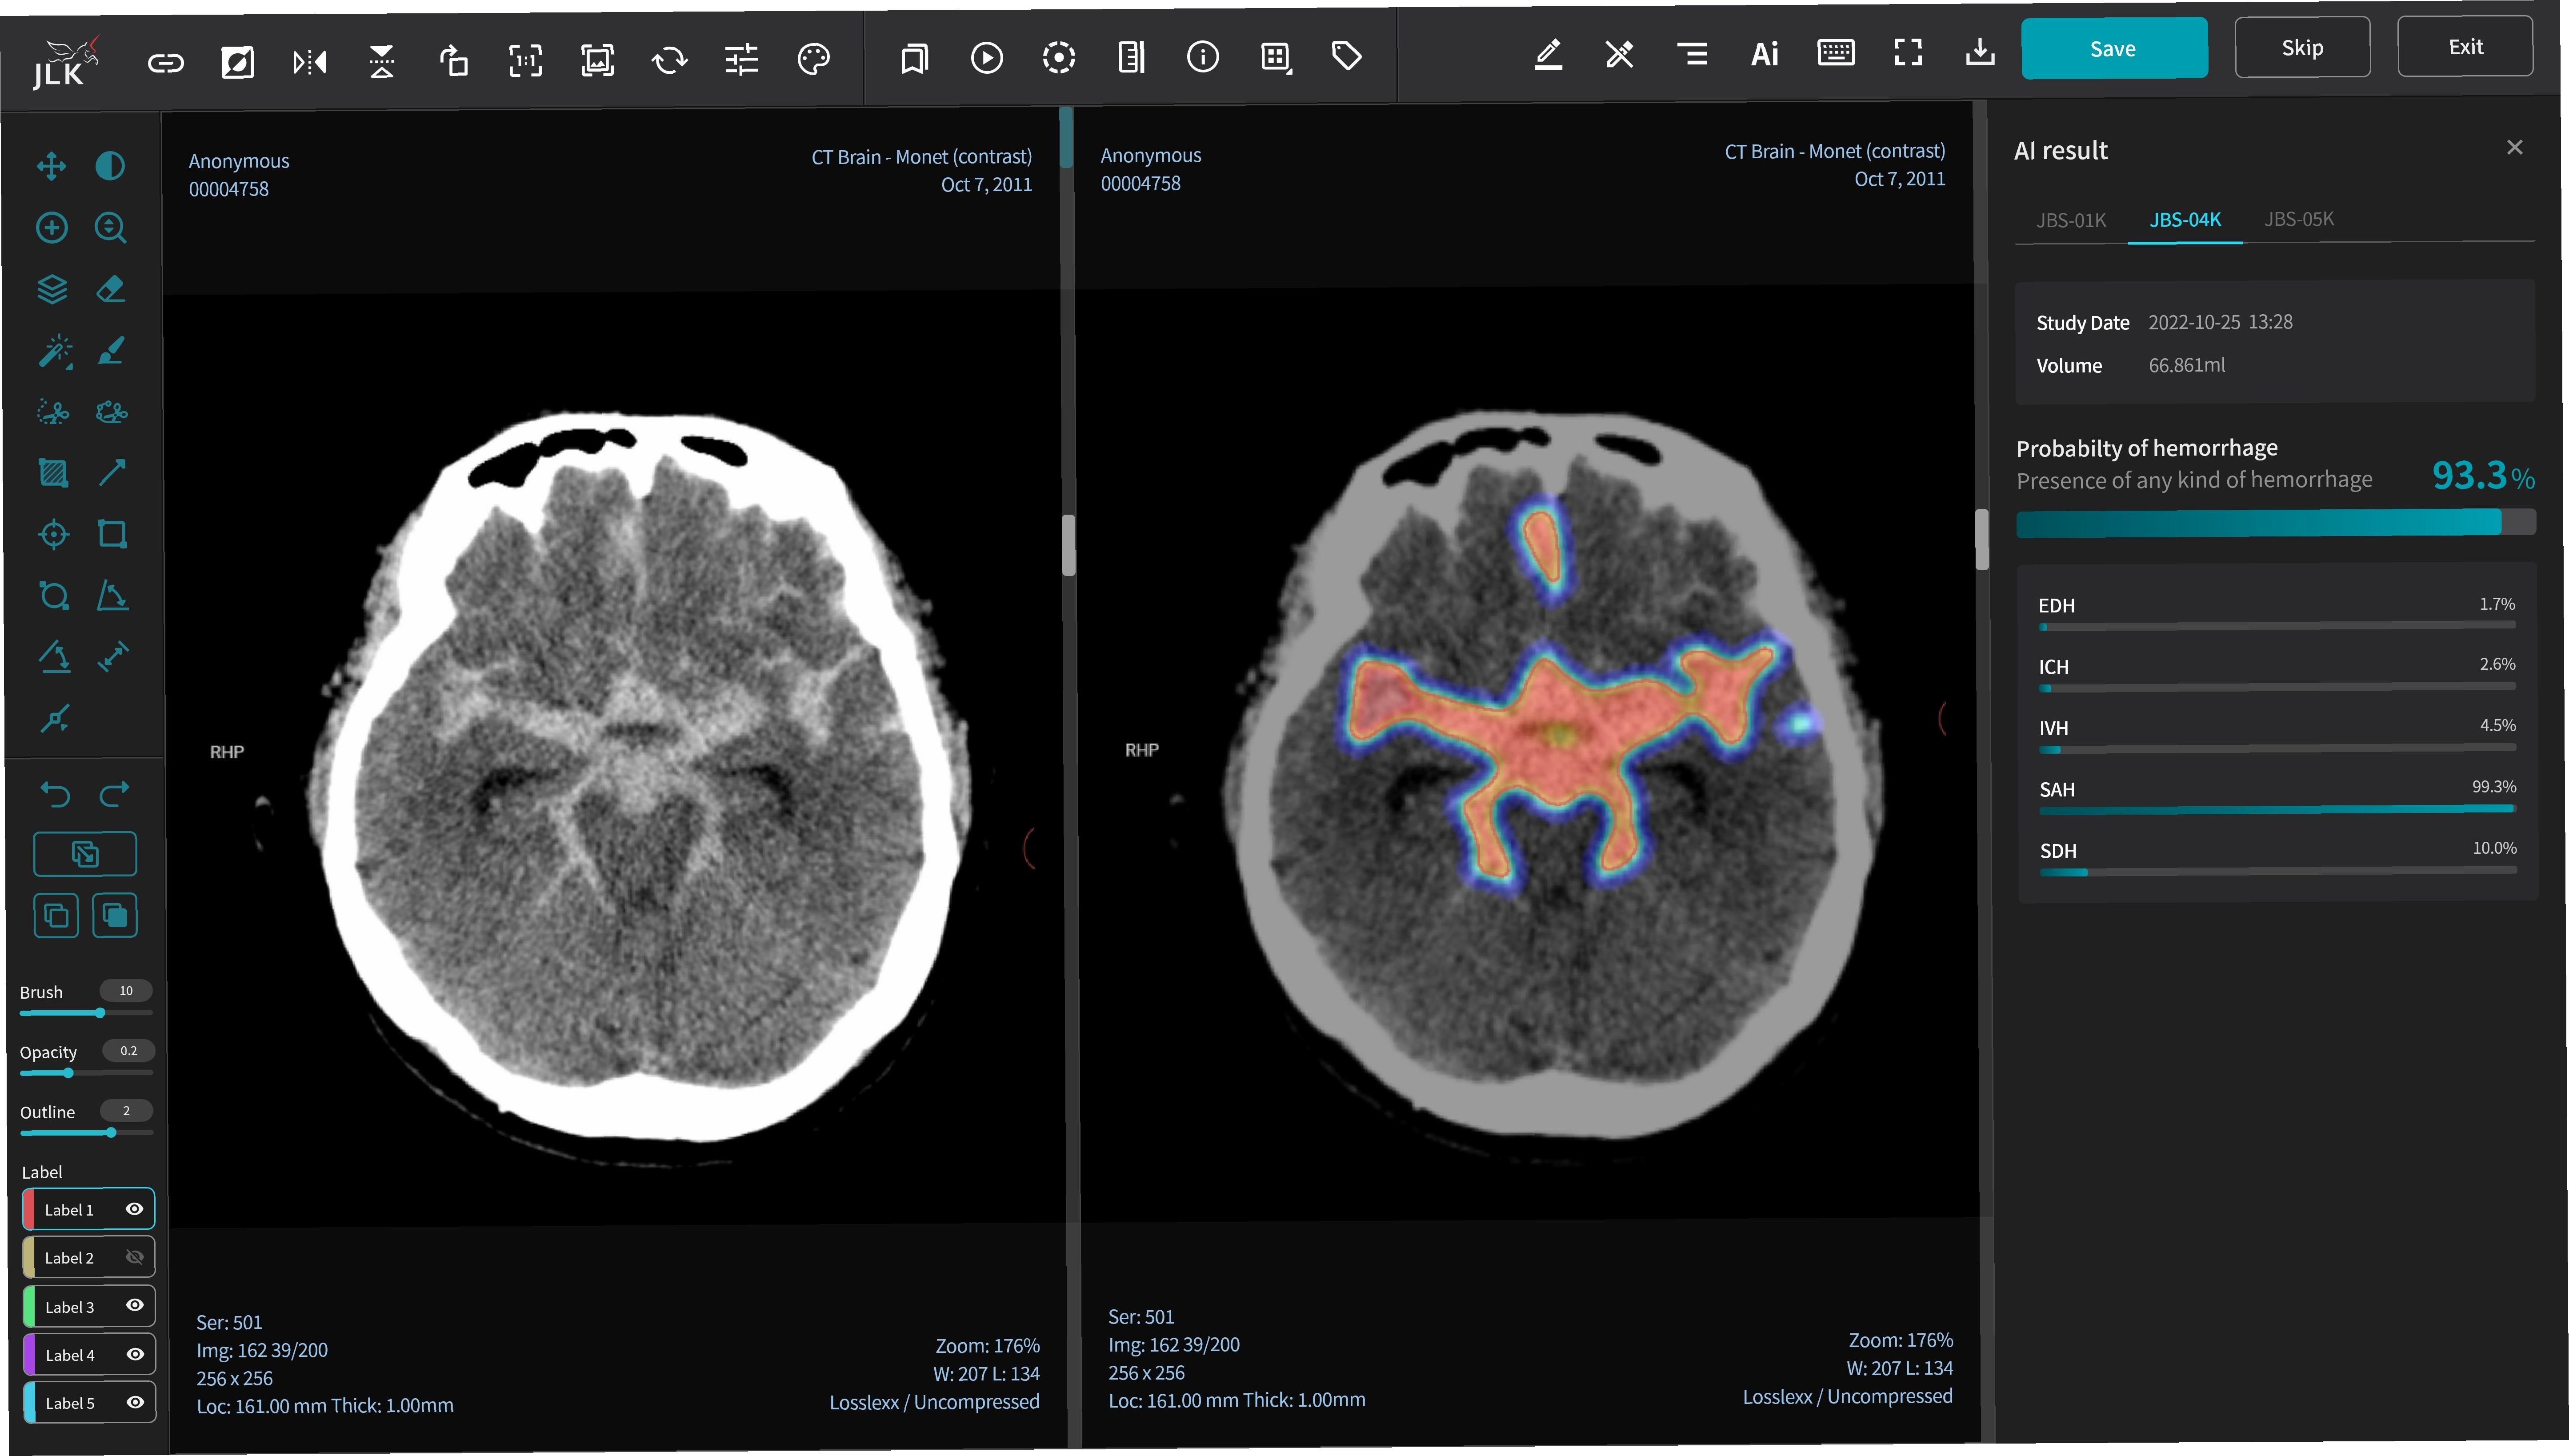

AI 기술은 뇌졸중 진단 분야에서 괄목할 만한 발전을 이루고 있습니다. 특히 영상 분석 기술을 통해 CT, MRI 등의 뇌 영상 데이터를 빠르고 정확하게 분석하여 뇌출혈, 뇌경색의 위치와 범위를 파악할 수 있습니다. AI는 뇌졸중의 골든 타임을 확보하는 데 기여하며, 의료진의 진단 정확도를 향상시키고, 환자 맞춤형 치료 계획을 수립하는 데 도움을 줍니다. AI 기반의 진단 시스템은 응급 상황에서 의료진의 의사 결정을 돕고, 환자의 생존율을 높이는 데 기여할 수 있습니다. AI는 뇌졸중 환자의 초기 진단뿐만 아니라, 재발 위험을 예측하고 예방하는 데에도 활용될 수 있습니다. AI 기술의 발전은 뇌졸중 진단 분야의 혁신을 넘어, 의료 서비스의 질을 전반적으로 향상시키는 데 기여할 것입니다. AI는 방대한 양의 의료 데이터를 학습하고 분석하여, 인간의 한계를 뛰어넘는 정확도와 효율성을 보여줍니다. AI 기술은 뇌졸중 환자의 생존율을 높이고, 삶의 질을 개선하는 데 중요한 역할을 할 것입니다.